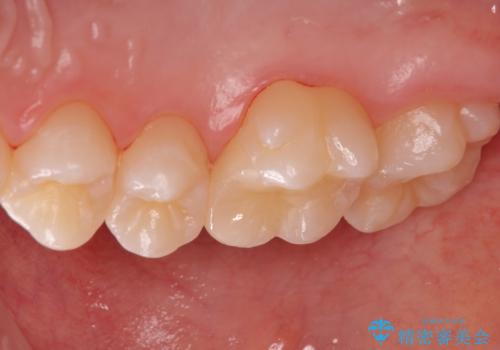

歯と歯の間の虫歯 セラミックインレーでの治療

- 検査の結果、レントゲン画像上で虫歯が確認されたため治療をしていくこととなりました。

白くて精度の高いものをご希望されたためセラミックインレーでの治療を行いました。

- 右上6 セラミックインレー 77,000円費用は治療当時の料金となります

小さな段差もないような適合の良い修復物は他の修復物に比べて今後の虫歯リスクを抑えることができます。